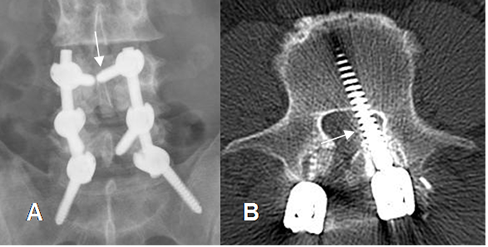

Fig 135. Mal posición de tornillos.

A: Rx AP. Tornillo superior izquierdo muy medializado, que cruza la línea media.

B: TAC axial. Tornillo izquierdo mal ubicado, ocupando la región paramediana del canal.